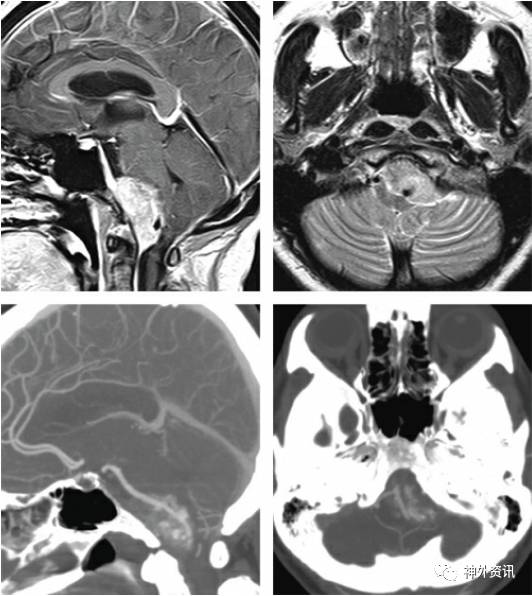

必要时,术前影像检查需包括血管情况,行CTA(V)或MRA(V) 检查来评估动静脉结构的位置,以利于手术处理。颅底的静脉尤其重要,它们的损伤常常会导致严重的静脉性梗死。

图2. 这是一例以平衡障碍和舌下神经麻痹为主诉的枕骨大孔腹侧脑膜瘤资料。CTA检查对发现肿瘤的钙化范围以及包绕椎动脉的情况非常有帮助。最终做到了肿瘤次全切除。

例如,Labbe静脉的位置会限制或改变经岩骨入路。使用高分辨率CT可以观察颞骨的解剖结构以及肿瘤(如脑膜瘤)侵犯骨质的情况。有时候血管造影也很有必要,比如外科医生在手术前对颈静脉球瘤进行栓塞治疗。如何避开致命而重要的颅内血管往往决定了手术入路的选择。